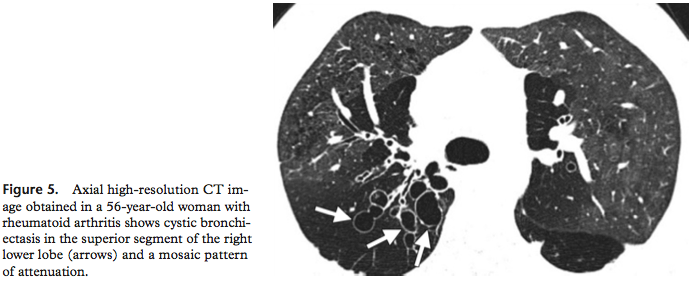

3. Bronchiectasis

rheumatoid arthritis의 약 30%에서 관찰된다.